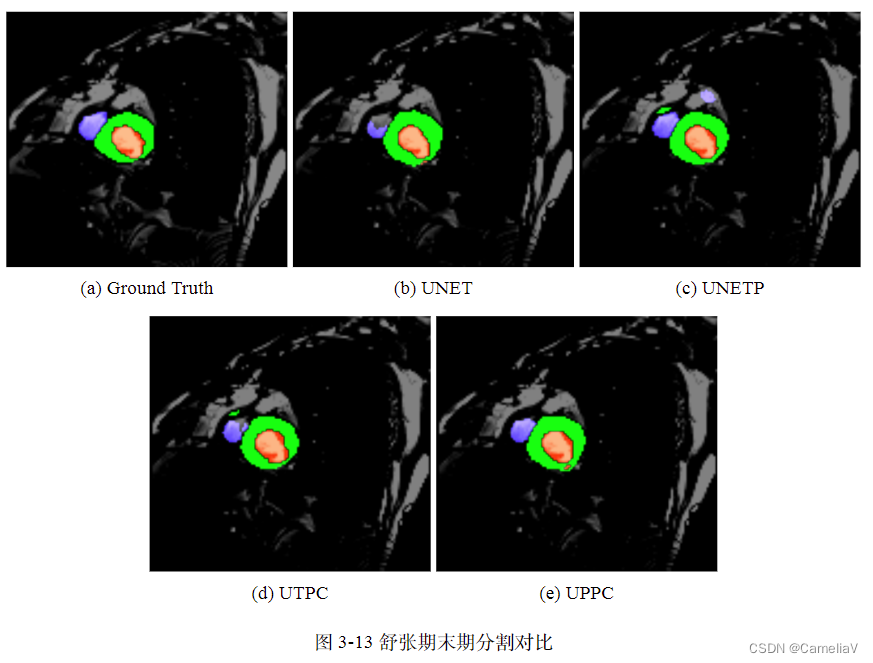

图片(带子图)

如果图片带有多余背景,可以先用PS去除

\begin{figure}[H]

\centering

\begin{subfigure}{0.325\linewidth}

\centering

\includegraphics[width=\linewidth]{fig/1-gt.png}

\caption{Ground Truth}

\label{1-gt}

\end{subfigure}

\centering

\begin{subfigure}{0.325\linewidth}

\centering

\includegraphics[width=\linewidth]{fig/1-unet.png}

\caption{UNET}

\label{1-unet}

\end{subfigure}

\centering

\begin{subfigure}{0.325\linewidth}

\centering

\includegraphics[width=\linewidth]{fig/1-unetp.png}

\caption{UNETP}

\label{1-unetp}

\end{subfigure}

\centering

\begin{subfigure}{0.325\linewidth}

\centering

\includegraphics[width=\linewidth]{fig/1-utpc.png}

\caption{UTPC}

\label{1-utpc}

\end{subfigure}

\centering

\begin{subfigure}{0.325\linewidth}

\centering

\includegraphics[width=\linewidth]{fig/1-uppc.png}

\caption{UPPC}

\label{1-uppc}

\end{subfigure}

\caption{舒张期末期分割对比}

\label{1-result}

\end{figure}